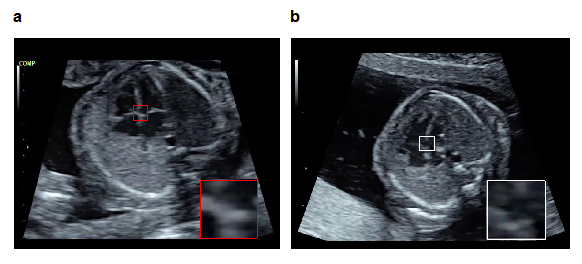

次にアノテーション済み正常データで学習した物体検知技術を用いて、検査対象の超音波画像から心臓の部位を検知します。物体検知技術は検査画像中からも人に近い精度で特定の部位を検知できます。したがって、物体検知によって得られた部位の検知状況と正常な心臓の部位の位置とを比較することによって、多少の陰影が入り込んだ不完全な検査画像であってもロバストな異常検知が実現されます。具体的には、以下の手順で異常を検知します(図1、特許出願中)。

図1 物体検知技術を活用した胎児心室中隔の異常検知例

さらに、その技術を用いて、超音波検査の動画上に映るべき胎児心臓と周辺臓器の各部位が実際に映っているかを「確信度(AI自身が予測に対して、どの程度確信を持っているかを示す値)」として高速で算出し、検査画面上にリアルタイムで表示する胎児心臓超音波スクリーニングシステムを構築しました(図2、特許出願中)。

図2 今回開発した、胎児心臓超音波スクリーニング異常検知システム